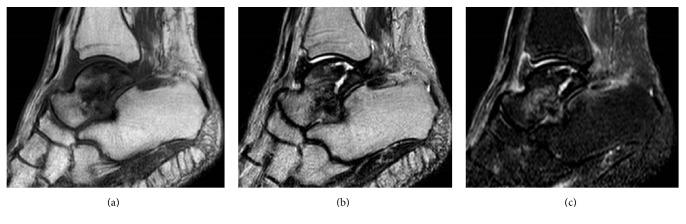

Two women aged 65 years and 78 years presented to our center with idiopathic necrosis of the talus. In both cases, imaging examinations showed collapse and sclerotic changes of the talar body caused by the necrosis. Both women underwent resection and placement of a third-generation custom-made alumina ceramic total talar prosthesis. Immobilization of the ankle in a short-leg cast for 3 weeks was followed by early rehabilitation. One year and 6 months after surgery, both women were able to walk without pain. Their Japanese Society for Surgery of the Foot ankle-hindfoot scale scores improved from 22 and 29/100 points to 90 and 95/100 points, respectively. To the best of our knowledge, the successful treatments of these two rare cases of idiopathic necrosis of the talus are among only a few reported cases of using a third-generation alumina ceramic prosthesis.

两名年龄分别为65岁和78岁的女性因距骨特发性坏死前来我院就诊。在这两个病例中,影像学检查均显示坏死导致距骨体塌陷和硬化改变。两名女性均接受了第三代定制氧化铝陶瓷全距骨假体的切除和植入手术。踝关节用短腿石膏固定3周后进行早期康复治疗。术后1年零6个月,两名女性均能无痛行走。她们的日本足踝-后足外科学会评分分别从22分和29/100分提高到90分和95/100分。据我们所知,这两例罕见的距骨特发性坏死的成功治疗是仅有的几例使用第三代氧化铝陶瓷假体的报道病例。